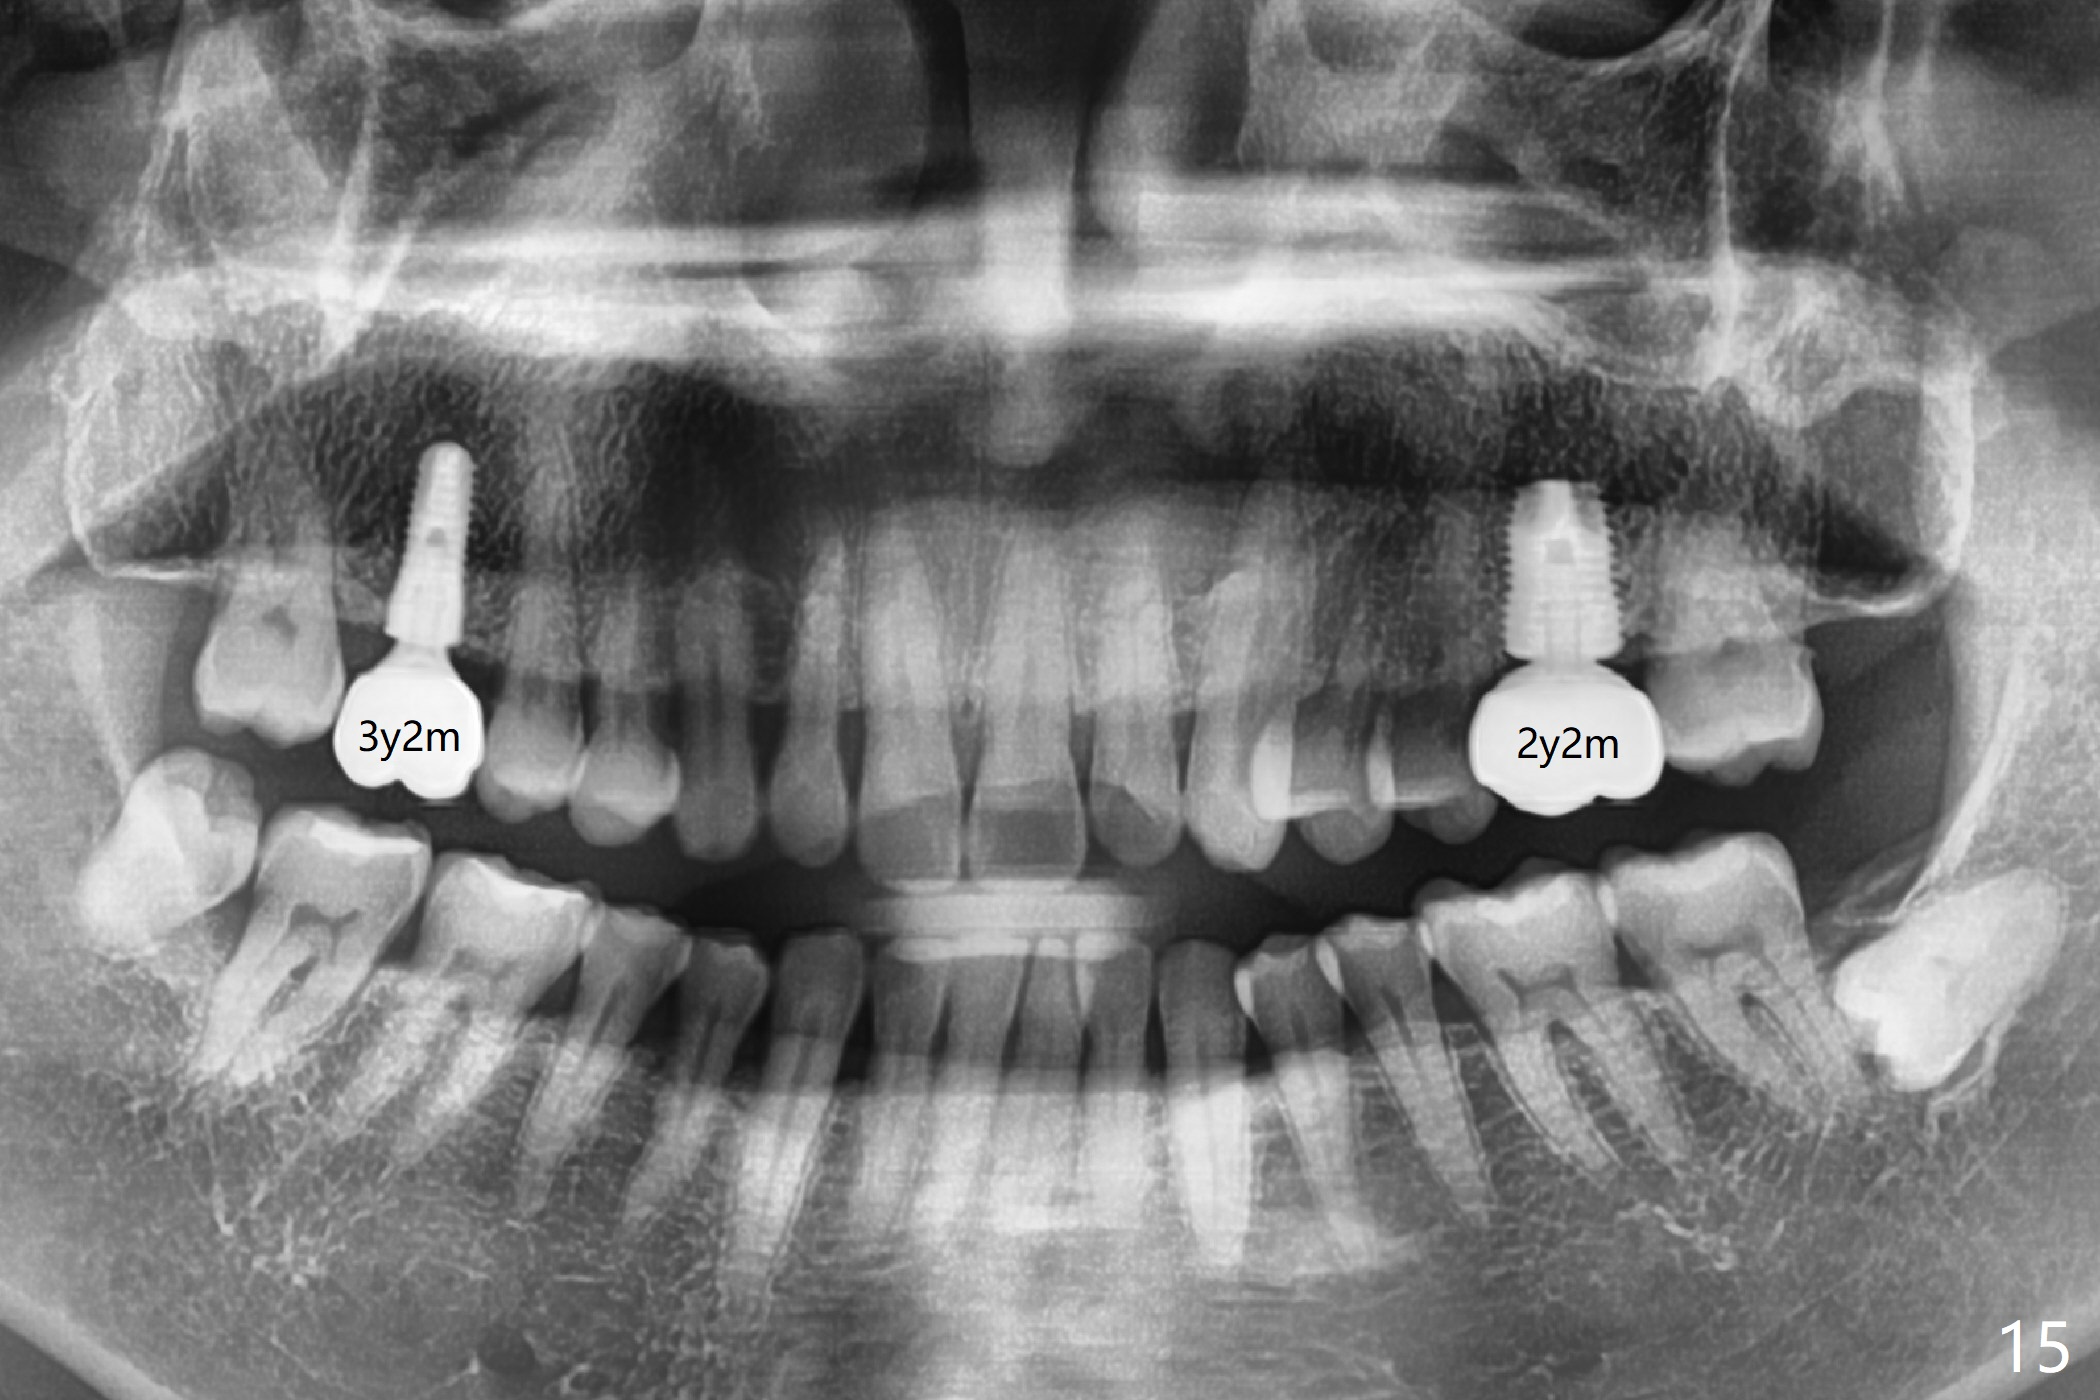

The crowns at #3 and 14 have been cemented for 3 years 2 months and 2 years 2 months, respectively (Fig.15).